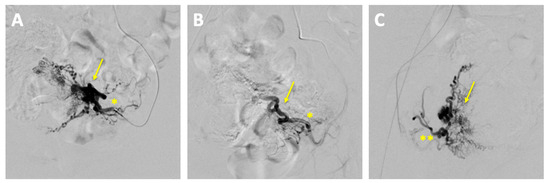

The embolization was performed by the department of interventional radiology. The left uterine artery was successfully embolized with 15 mL of Embozene 900 µm, achieving complete stasis of the blood flow. Post-procedural angiography demonstrated a significant reduction in vascularity with markedly slowed blood flow (Figure 4).

Figure 4. Pre- and post-embolization angiography of uterine arteriovenous malformation (AVM). (A) Pre-embolization angiography: superselective catheterization of the left uterine artery (*) demonstrating the vascular supply to the AVM (arrow); (B) post-embolization angiography (left uterine artery *): contrast injection via the left uterine artery showing successful embolization with no residual filling of the AVM (arrow) from the left side; (C) post-embolization angiography (right uterine artery): contrast injection via the right uterine artery (**) confirming no residual AVM filling from the right side.